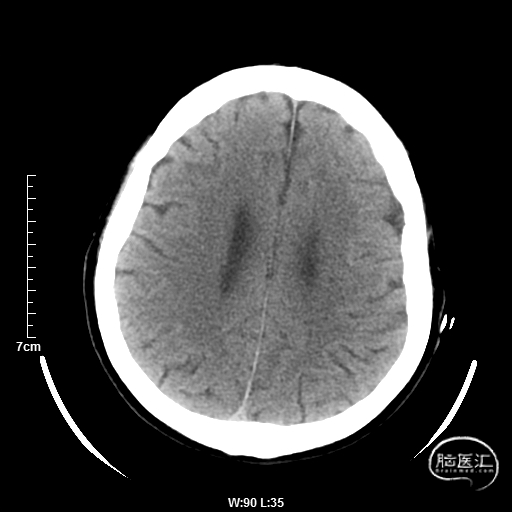

颅脑CT:未见明显缺血/出血病灶。

CTA提示:右侧椎动脉纤细,左侧椎动脉V1、V4段纤细。

术后CT:未见明显脑出血,双侧小脑低密度影。